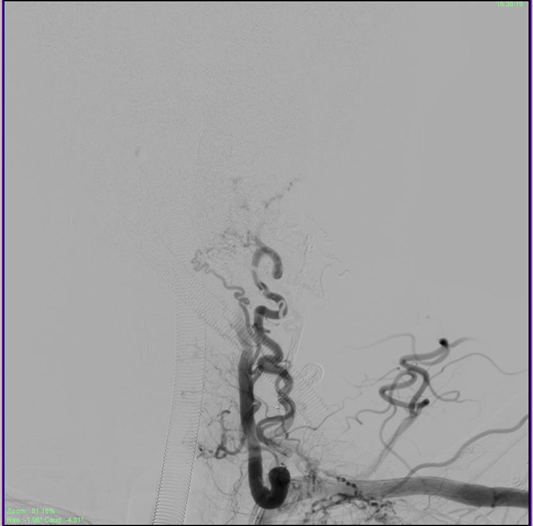

The patient was then administered general anesthetic. IV heparin of approximately 1000U was administered every hour further on and a Heparin flush was connected to the femoral sheath. The 5F short sheath was then exchanged for a Neuron Max 088 Sheath which was placed under fluoroscopic guidance into the left proximal subclavian artery. A 5F Navien catheter was then advanced into the Left Vertebral Artery railroaded on a 035 guidewire. Over this the Neuron Max catheter was moved co-axially into the proximal vertebral artery as well. An Echelon Microcatheter was then taken over the 014 Traxcess microwire and feeders from the distal V2 segment of the vertebral artery were selectively catheterized and visualized. The large lateral feeder which was significantly dilated was chosen for onyx injection (Figure 4). DMSO was injected to fill the dead space of the microcatheter and Onyx was injected under multiple blank roadmap guidance into the feeder to fill the EDAVF sac partially. Reflux into the main vertebral artery was noted, after which the injection of the onyx was stopped. Post injection films showed complete obliteration of the feeders from the vertebral artery (Figure 5).

Figure 4 Injection of the large lateral feeder showing filling of the fistula.

Figure 5 Partial obliteration of the EDAVF after onyx injection of the vertebral feeders, showing stasis in the draining veins.

The sheath was then repositioned into the left Costocervical trunk. (The Echelon microcatheter was then advanced distally into the branch over a microwire (Figure 6). Multiple vials of Onyx were injected to the fistula achieving complete obliteration of the venous sac in just over 55 minutes approximately. The Onyx was also seen filling the adjacent feeder branches as well obliterating all arterial feeders to the EDAVF. A check angiogram of bilateral subclavian arteries and the right vertebral artery showed considerable slowing of flow into the EDAVF with approximately 80-90% obliteration of the venous sac (Figure 7).

Figure 6 Deep Cervical Feeders identified, after injecting the costocervical trunk.

Figure 7 Check angiogram showing complete obliteration of the compressive venous sac post embolization, and stasis in the draining veins which will eventually empty and close.